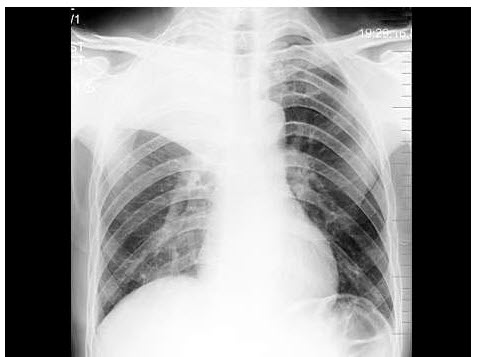

57、单项选择题

女,36岁,发热,胸痛咳脓痰10余天,胸片如图,最可能的诊断为()

A.左下肺周围型肺癌并空洞形成

B.左下肺脓肿

C.左下肺空洞型肺结核

D.左侧包裹性液气胸

E.急性胃扩张